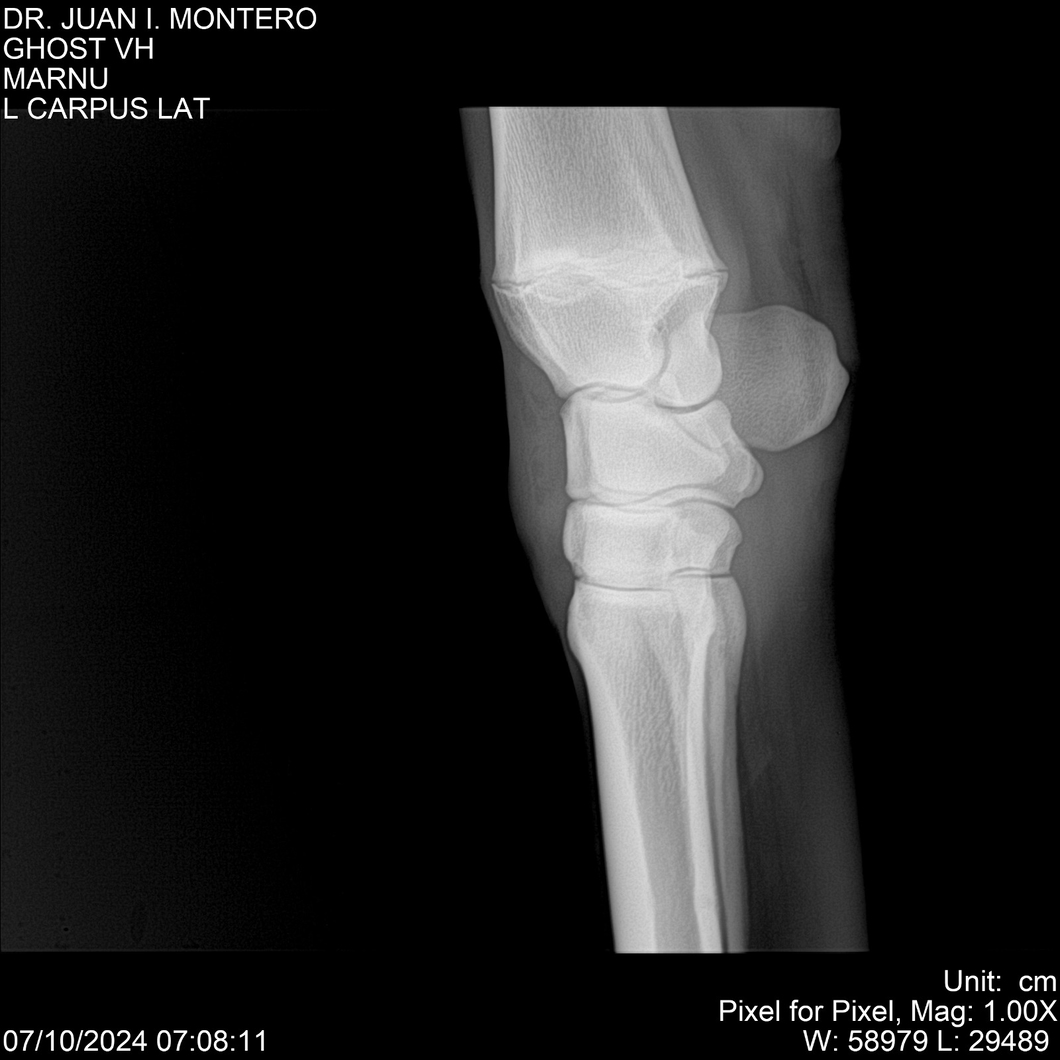

LOTE 15, GHOST VH 🔥 🔥 🔥 Lote Anterior Volver al remate Lote Siguiente Ficha Contacto Montevideo - Ficha del Lote Identificador: #282525 Categoría: Yeguarizos Montevideo - 69 Visualizaciones ClicData Contacto Empresa: Abelenda N. R., Walter Hugo Nombre*: Teléfono* : E-mail* : Mensaje Enviar Registrese gratis Este contenido Exclusivo está disponible sólo para usuarios registrados Ingresar